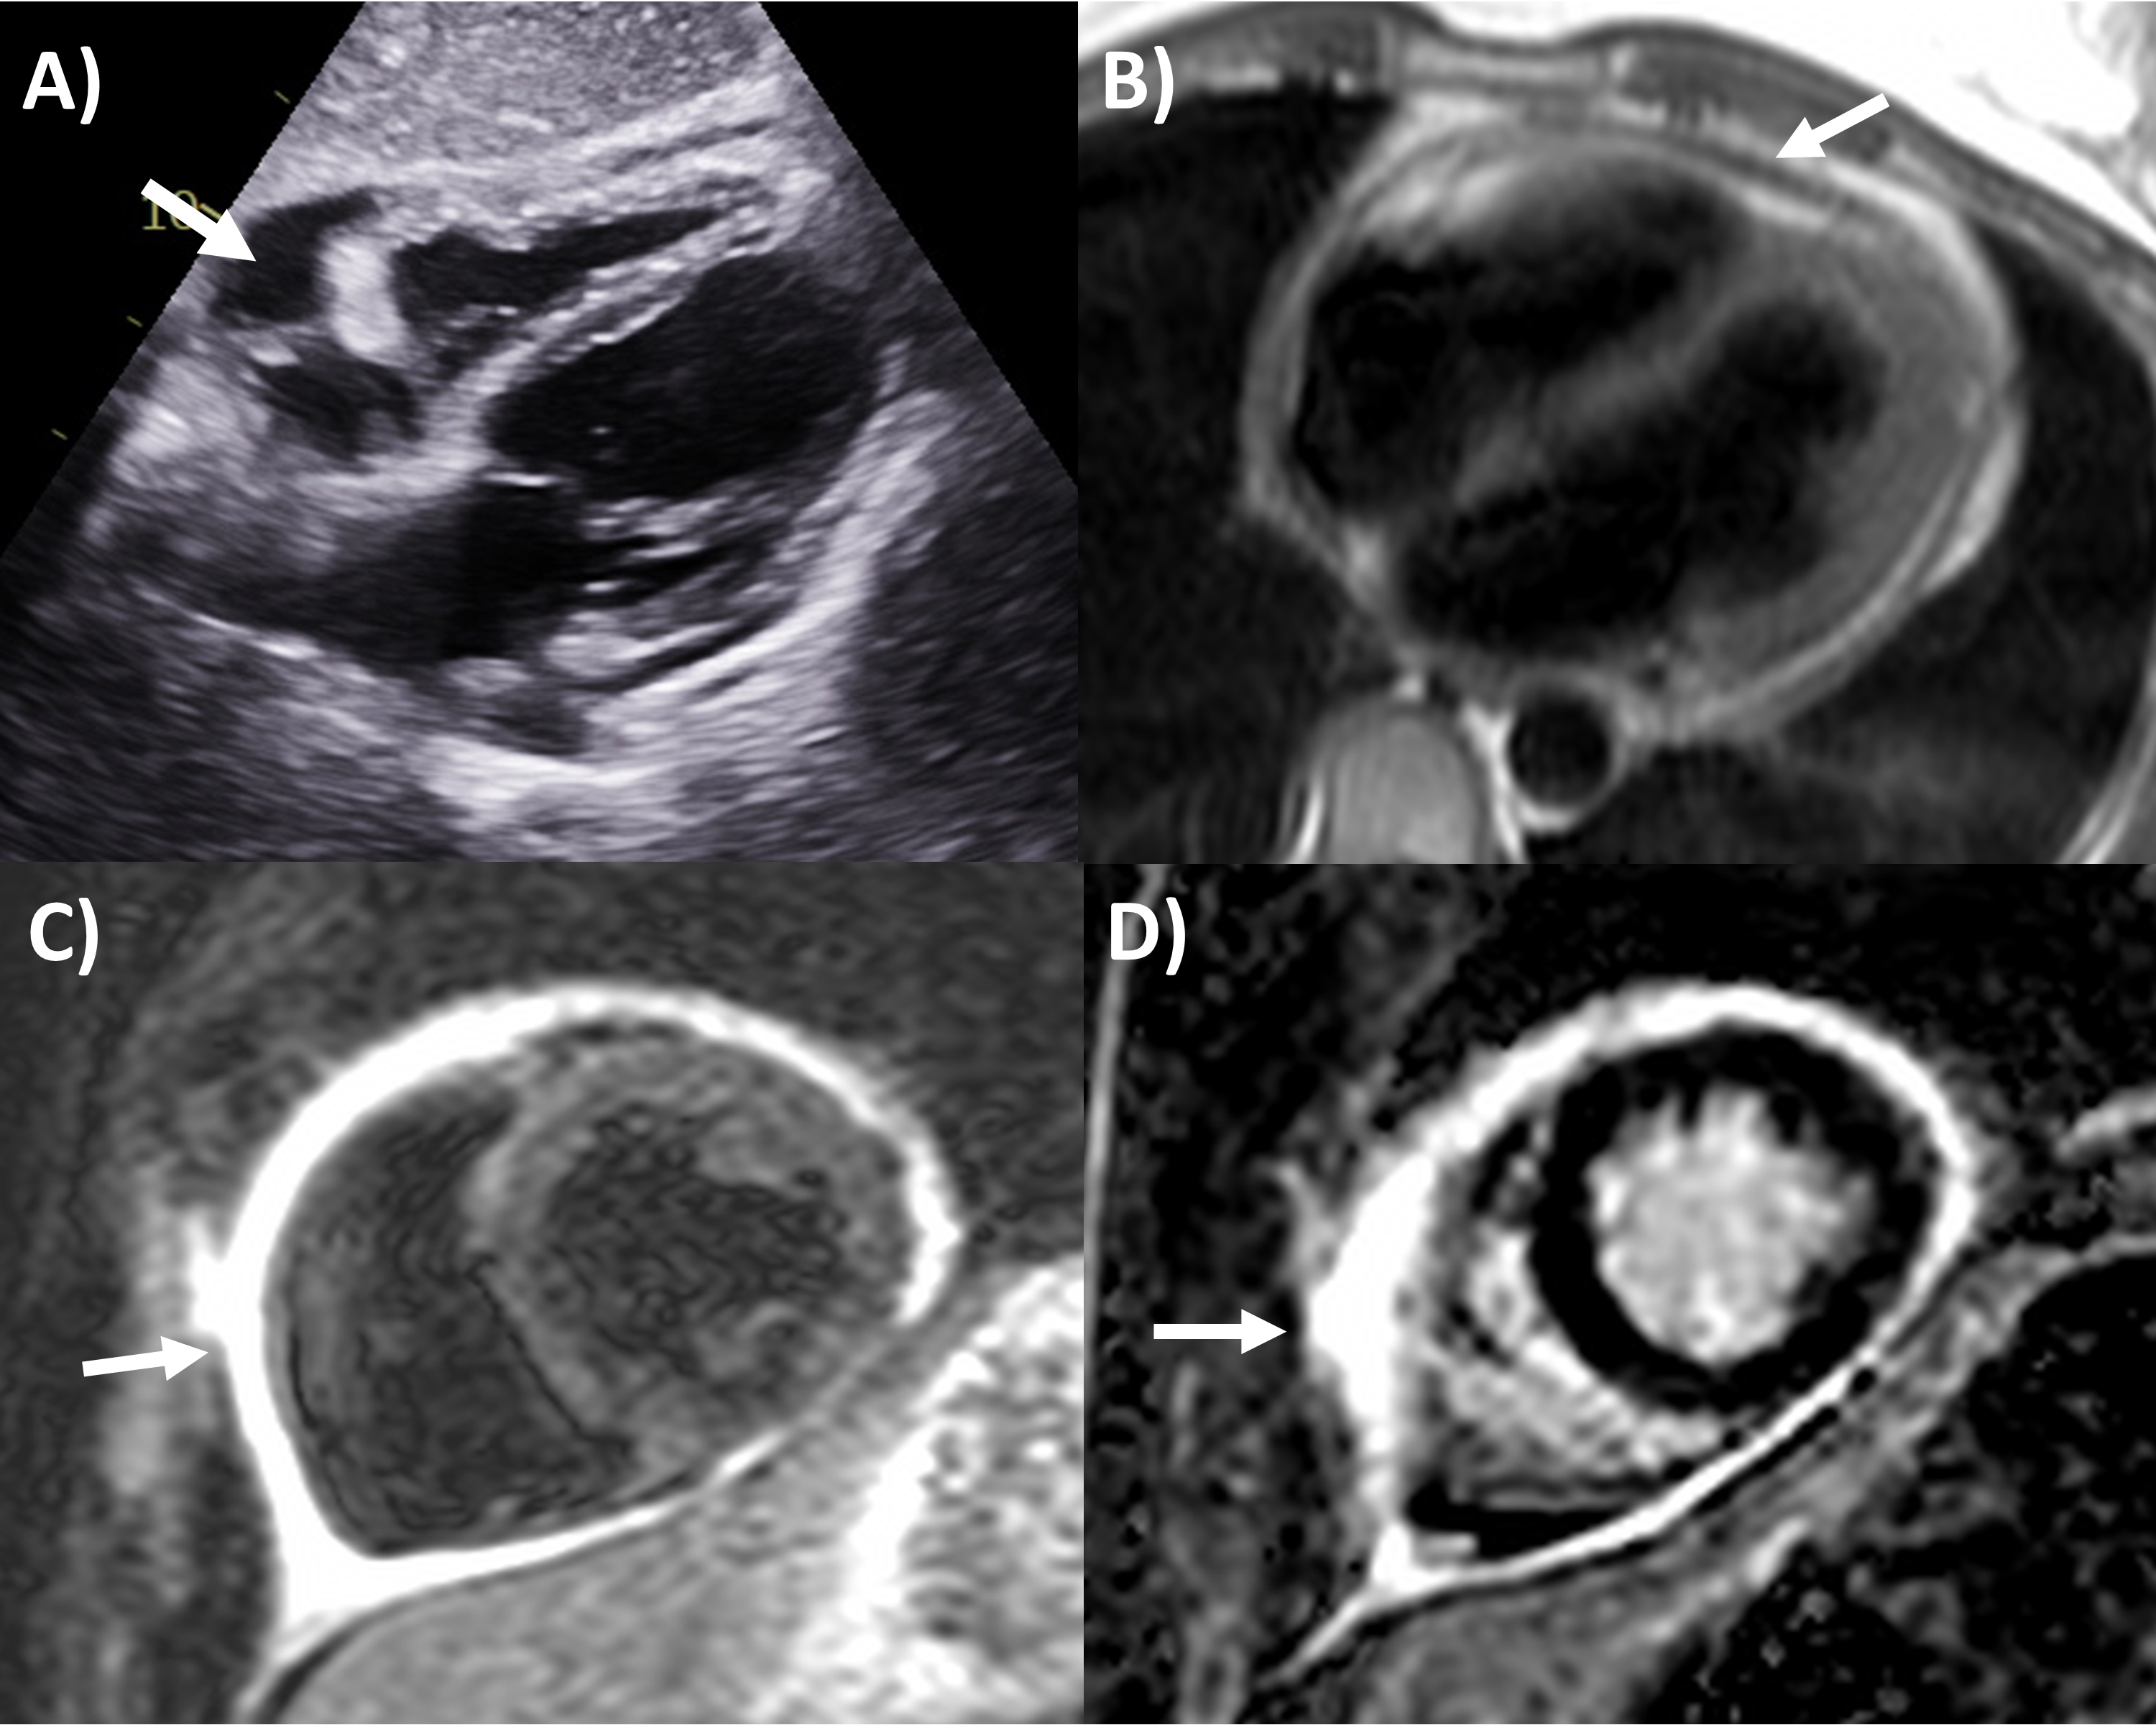

echocardiographic criteria according to guidelines (Fig. 2) include dilated

Fig. 2.Echocardiography evaluation of pericardial tamponade. (A)

Dilated inferior vena cava (2.7 cm) with minimal

Effusive-constrictive pericarditis is an increasingly recognized entity, where both pathological pericardial features (including tamponade) are concurrently present [2]. There is usually a significant pericardial effusion to start with, and the fluid can be organized, echogenic or loculated by echocardiography [2, 28]. The hallmark feature is that after pericardiocentesis is performed to remove the fluid, there is persistently elevated right atrial pressure, right and left ventricular end-diastolic pressures (with dip and plateau waveform) and prior echocardiography characteristics of constriction such as respirophasic septal shift emerge [2, 29].